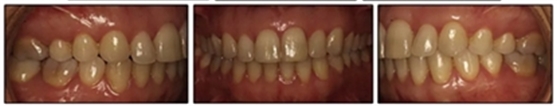

患者決定采用非手術(shù)治療方法,側(cè)貌沒(méi)有任何預(yù)期的變化。治療后面部照片(圖5)顯示她改善的微笑和側(cè)貌,包括尖牙保護(hù)合。由于先天性第一前磨牙缺失,右磨牙關(guān)系為III類。治療后牙齒石膏模型(圖6)顯示實(shí)體牙齒交錯(cuò)排列情況,并且全景X線片顯示可接受的牙根平行度而且沒(méi)有牙根吸收表現(xiàn)(圖7)。最終的頭影測(cè)量片(圖7)證實(shí)了面部評(píng)估,并且描跡圖顯示深覆蓋的改善,同時(shí)保持上頜切牙位置并通過(guò)測(cè)量ANB角度和Wits評(píng)估改善骨性II級(jí)關(guān)系(表)。治療前后的疊加圖顯示由于下頜切牙前傾的增加改善了下唇平衡(圖8)。如相關(guān)治療計(jì)劃所預(yù)測(cè)的那樣,B點(diǎn)出現(xiàn)。A進(jìn)行牙科錐形束計(jì)算機(jī)斷層掃描以記錄下頜前牙區(qū)的骨質(zhì)變化。如預(yù)期的那樣,由于治療導(dǎo)致該區(qū)域的骨量增加(圖9)。

放置上頜和下頜尖牙到尖牙的聯(lián)合保持器,并使用支持性上頜環(huán)繞Hawley保持器進(jìn)行夜間佩戴以加速關(guān)閉所有帶狀間隙。

最終評(píng)估結(jié)果如下:(1)美觀改善; (2)達(dá)到了生理功能; (3)患者對(duì)治療結(jié)果完全滿意; (4)上頜尖牙的角度和下頜切牙的傾斜度有所改善(表); (5)形成了穩(wěn)定的牙周終點(diǎn),并觀察到附著齦的厚度改善; (6)病人會(huì)從下頜前移中受益,但她不想改變她的側(cè)貌; (7)長(zhǎng)期變化(6年)是穩(wěn)定的,在B點(diǎn)再生的骨保持穩(wěn)定,咬合關(guān)系得到改善(圖10和11;表)。